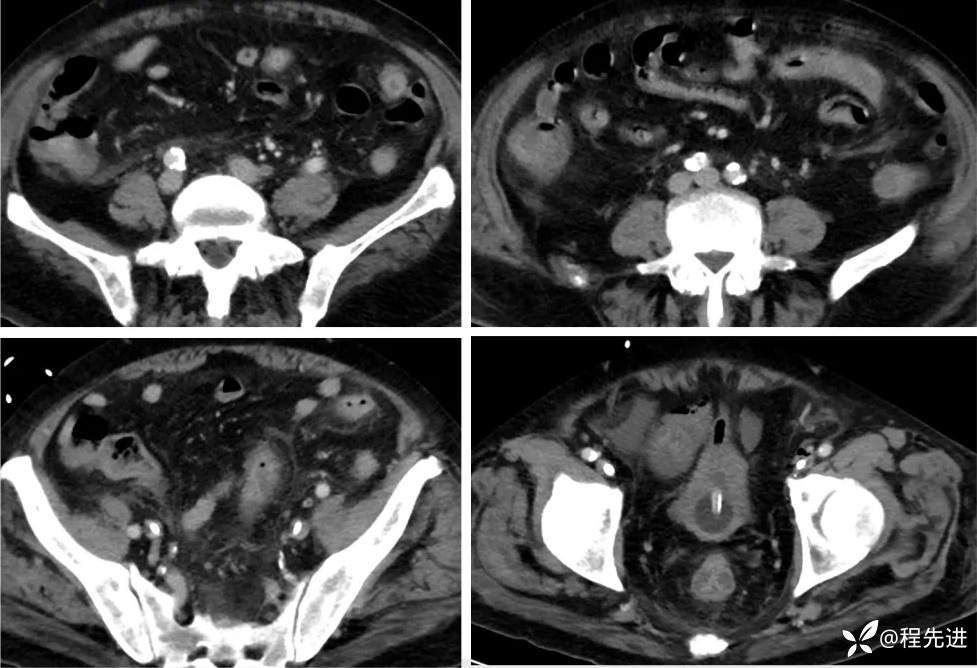

影像检查: